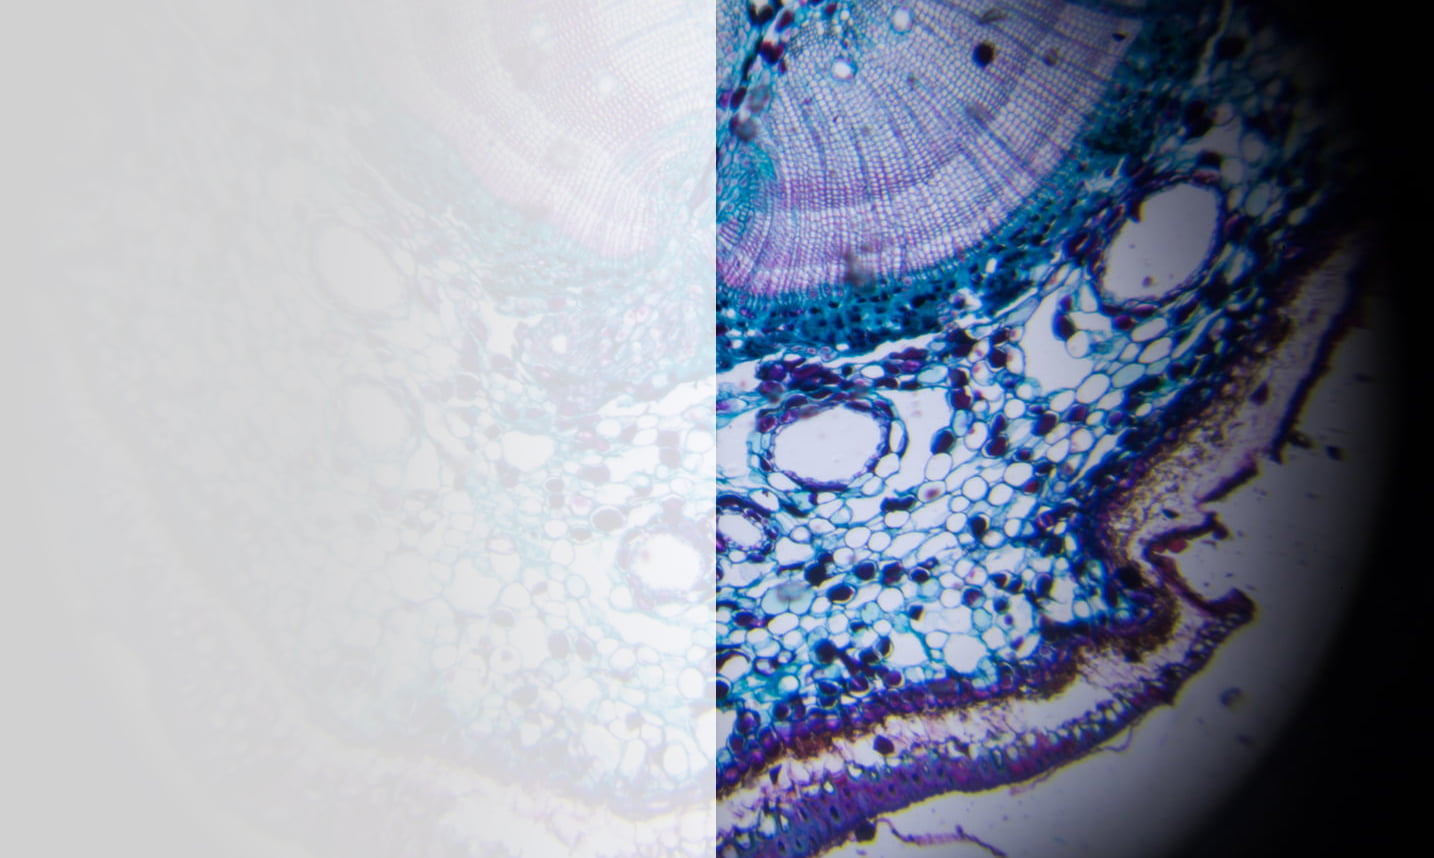

With higher and higher volumes of unstructured data generated across the healthcare sector on a daily basis, and more and more organisations exploring the possibilities offered by cutting-edge digital pathology, an effective Picture Archiving and Communication System (PACS) is a key part of an effective data management strategy and effortless cross-site collaboration.

Exponential-e offers a fully integrated PACS solution stack, delivered as a managed service, allowing Healthcare organisations to deploy their own launchpad for effective digital pathology in a matter of weeks, not months.